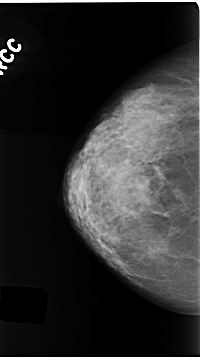

C_0175_1.RIGHT_CC

RIGHT_CC LINES 4704 PIXELS_PER_LINE 2600 BITS_PER_PIXEL 12 RESOLUTION 50 NON_OVERLAY